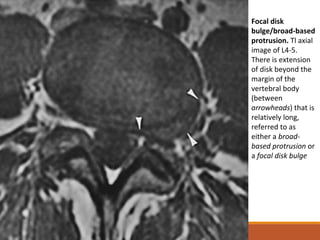

Focal disk

bulge/broad-based

protrusion. Tl axial

image of L4-5.

There is extension

of disk beyond the

margin of the

vertebral body

(between

arrowheads) that is

relatively long,

referred to as

either a broad-

based protrusion or

a focal disk bulge

Focal disk bulge/broad-based protrusion. Tlaxial image of L4-5. There is extension of disk beyond the margin of the vertebral body (between arrowheads) that is relatively long, referred to as either a broad- based protrusion or a focal disk bulge